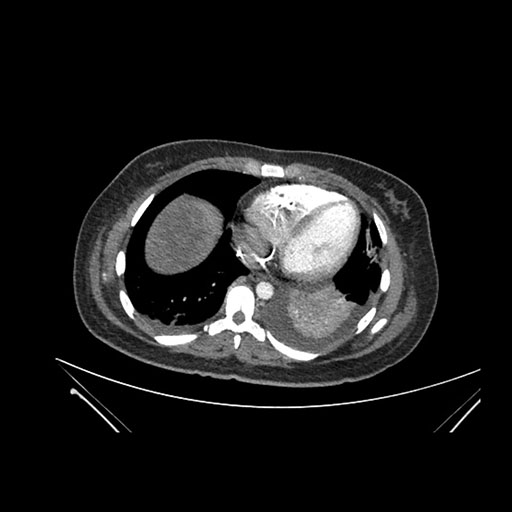

Imaging Analysis

Look through the patient's CT scan to identify any areas of concern for the necessary procedure.

Axial Venous

Based on initial findings, which issue(s) would you be most concerned about?